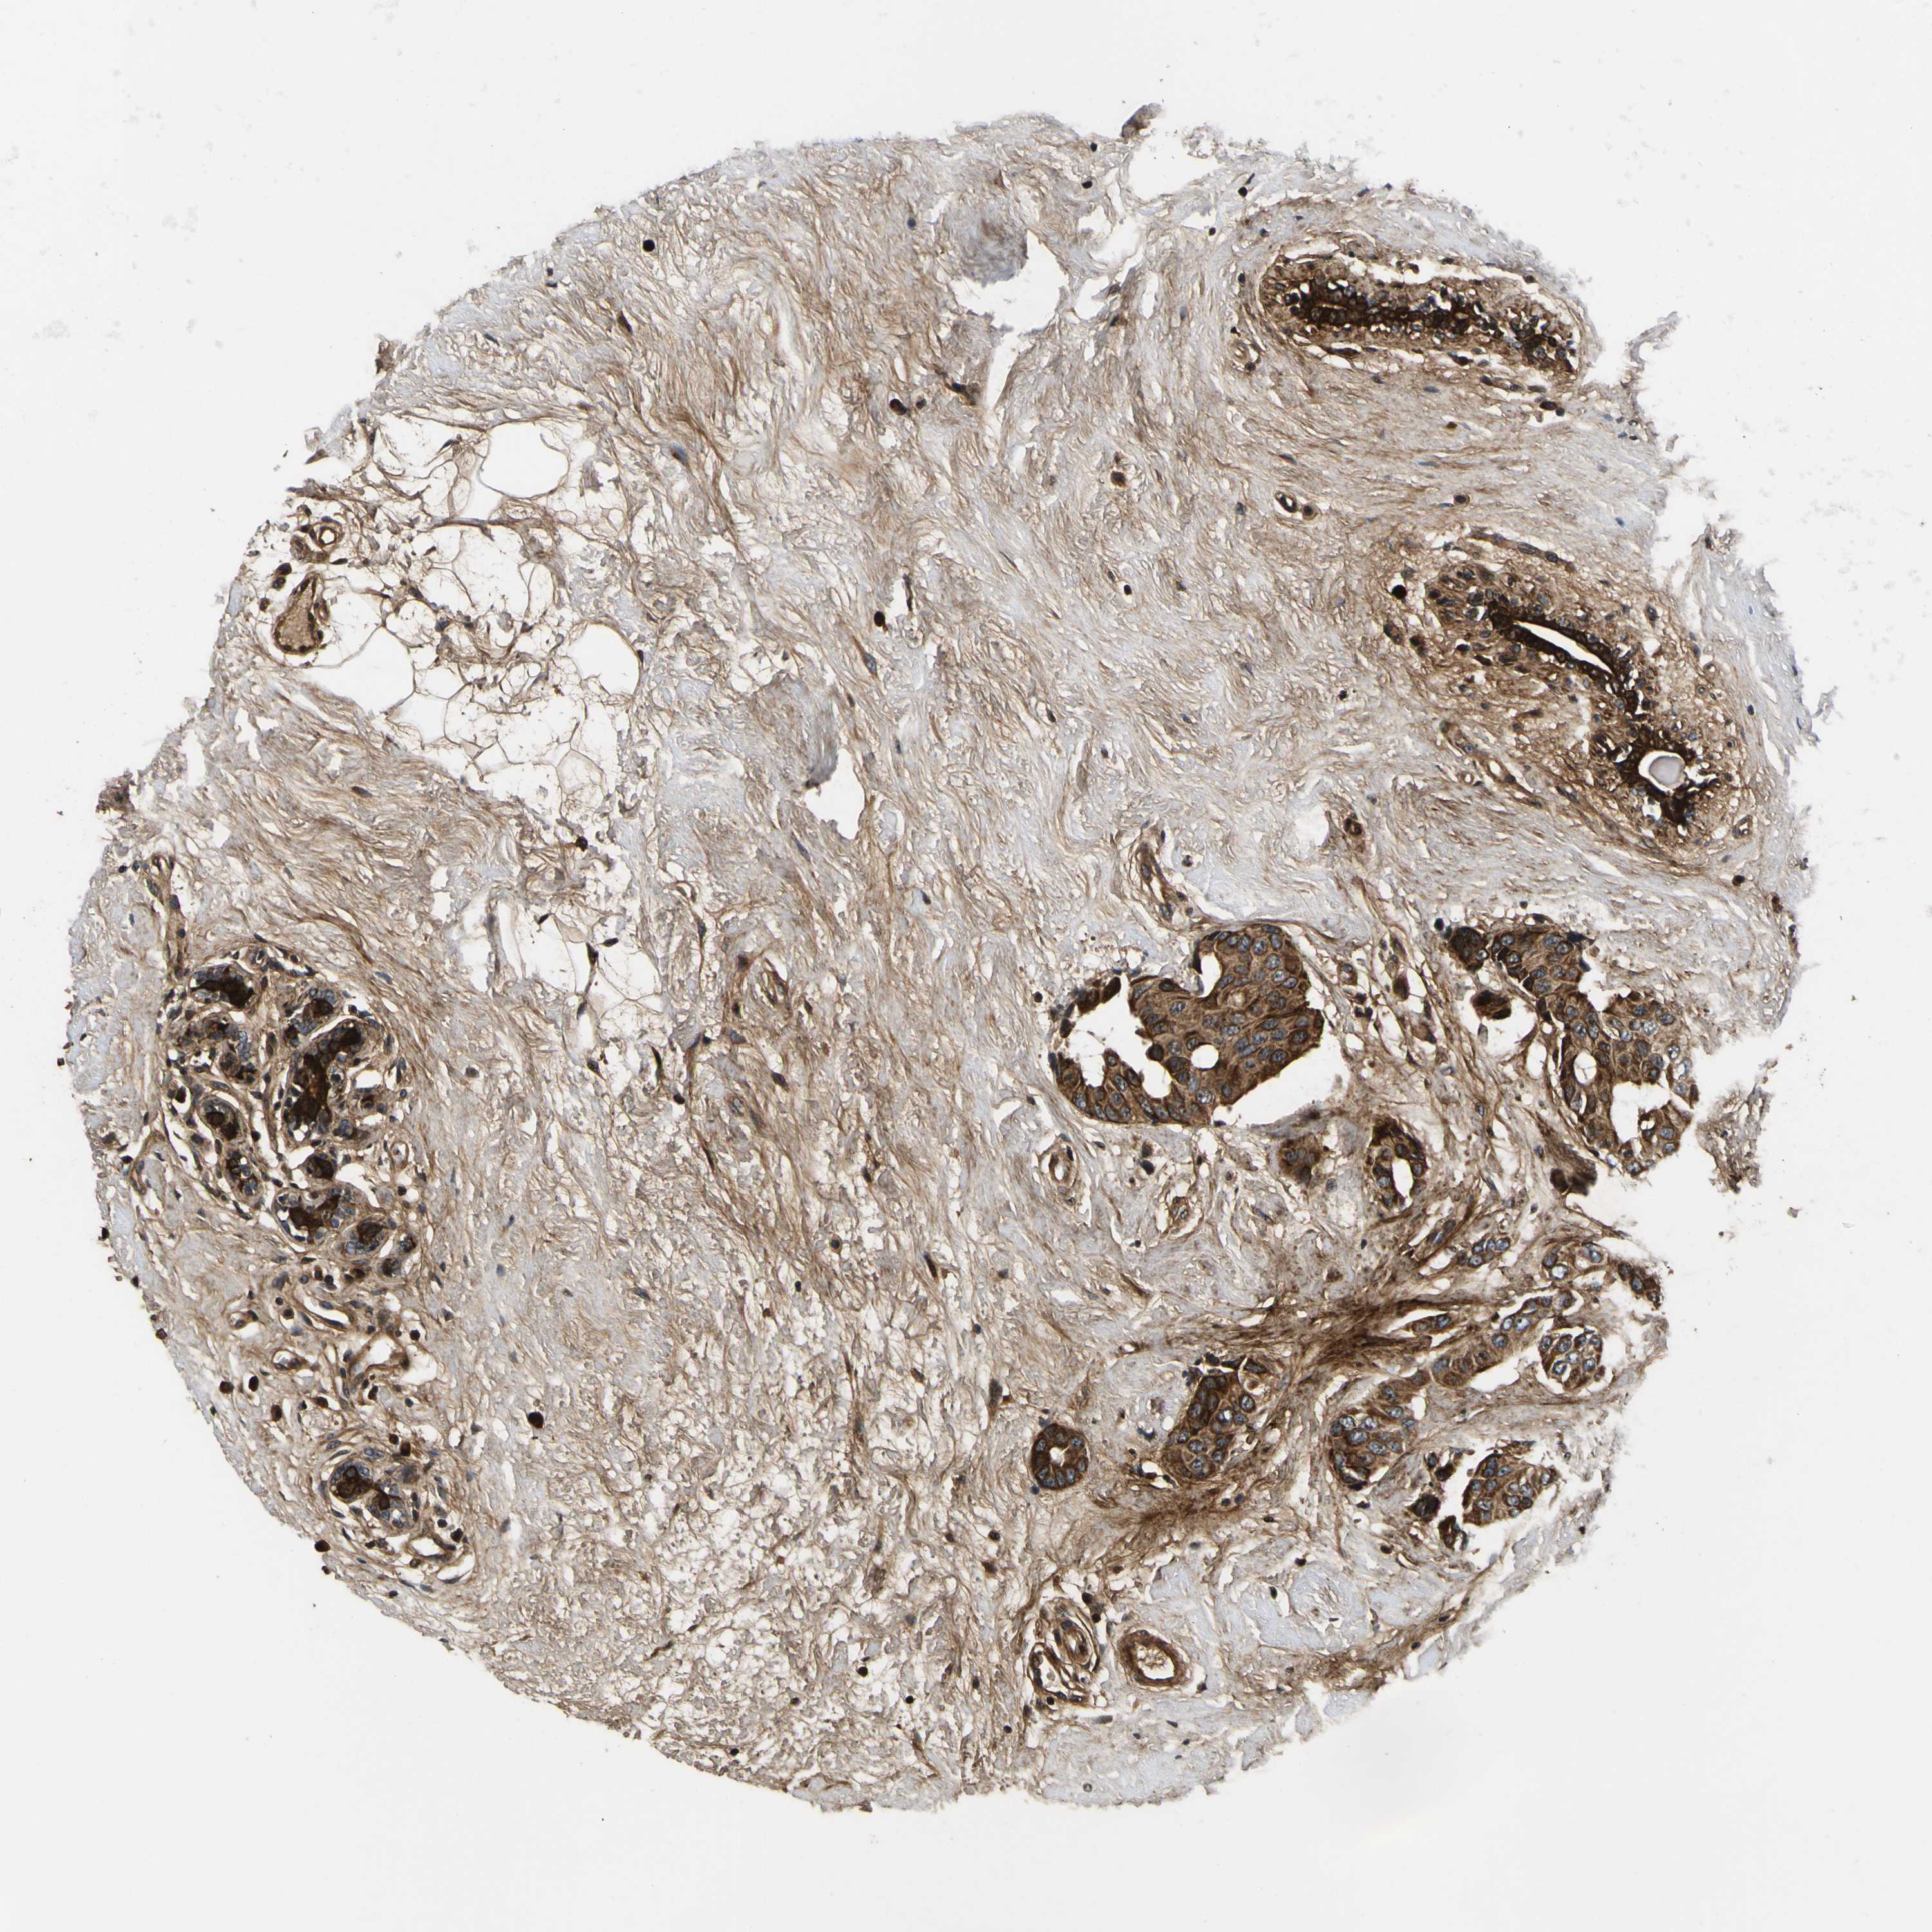

CANCER BREAST CANCER Show tissue menu

BRCA TCGA BRCA VALIDATION PROTEIN EXPRESSION